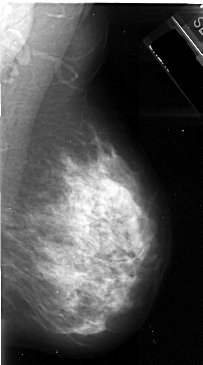

A_1072_1.LEFT_CC

LEFT_CC LINES 5161 PIXELS_PER_LINE 2701 BITS_PER_PIXEL 16 RESOLUTION 42 OVERLAY